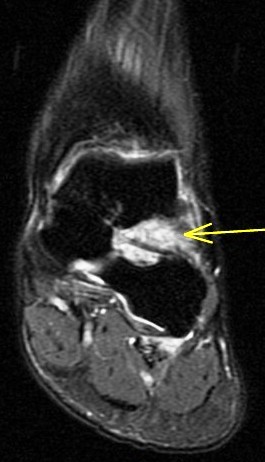

36 yo M s/p ankle sprain 7 months ago

Marked edema and scarring in the tarsal sinus. Has healed sprains of the ankle ligaments with scar remodeling (not shown). You can see where the ongoing pain is by the oil marker. I insist on having pain markers when possible. Reference article.

sinus tarsi syndrome ( RID3222 )